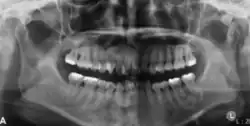

The radiographic features of central ossifying fibroma can be categorised according to the stages.

In its early stages, central ossifying fibroma (COF) appears as a small, well-defined radiolucent lesion due to its fibrous tissue content. Differential diagnoses at this stage include periapical pathology, central giant cell granuloma, and ameloblastoma.[22][23] As the lesion matures, it exhibits a mixed radiolucent-radiopaque appearance due to progressive calcification.[22] At this stage, it should be differentiated from other mixed jaw lesions such as fibrous dysplasia, calcifying epithelial odontogenic tumour, adenomatoid odontogenic tumour, and condensing osteitis.[22] In its mature form, COF may appear predominantly radiopaque, resembling lesions like odontomas, osteoblastomas, or osteosarcomas radiographically.

COF typically presents with well-defined, smooth, and often corticated borders. As a central lesion, it originates within the medullary bone and expands concentrically in all directions.[24] With growth, it may cause tooth displacement, root resorption, inferior displacement of the mandibular canal, and loss or alteration of the lamina dura of adjacent teeth.[25]

In conclusion, COF most commonly occurs in the mandible and expands from a central epicenter. Radiographically, it presents as a well-defined mixed-density lesion,[26] and Cone Beam CT (CBCT) plays a crucial role in its accurate diagnosis and assessment.